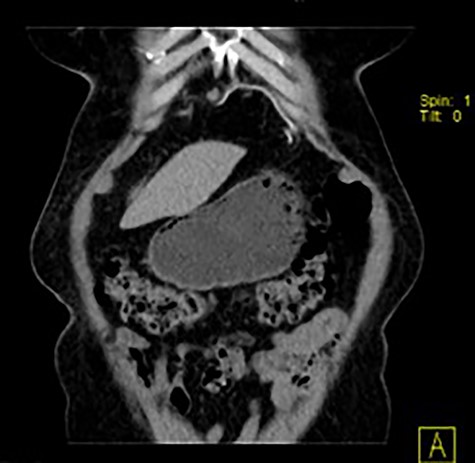

She had a chest X-ray done (Fig. 1) that showed widening of the mediastinum, as well as a few air-fluid levels, which raised suspicion of a diaphragmatic hernia. She also had a thoracic CT done (Fig. 2) that revealed a large hernia in the anterior mediastinum, containing transverse colon and a significant amount of ‘omentum,’ causing right side heart deviation.

(a–c) Axial, coronal and sagittal images, respectively, of thoracic and abdominal CT showing the localization of this hernia.